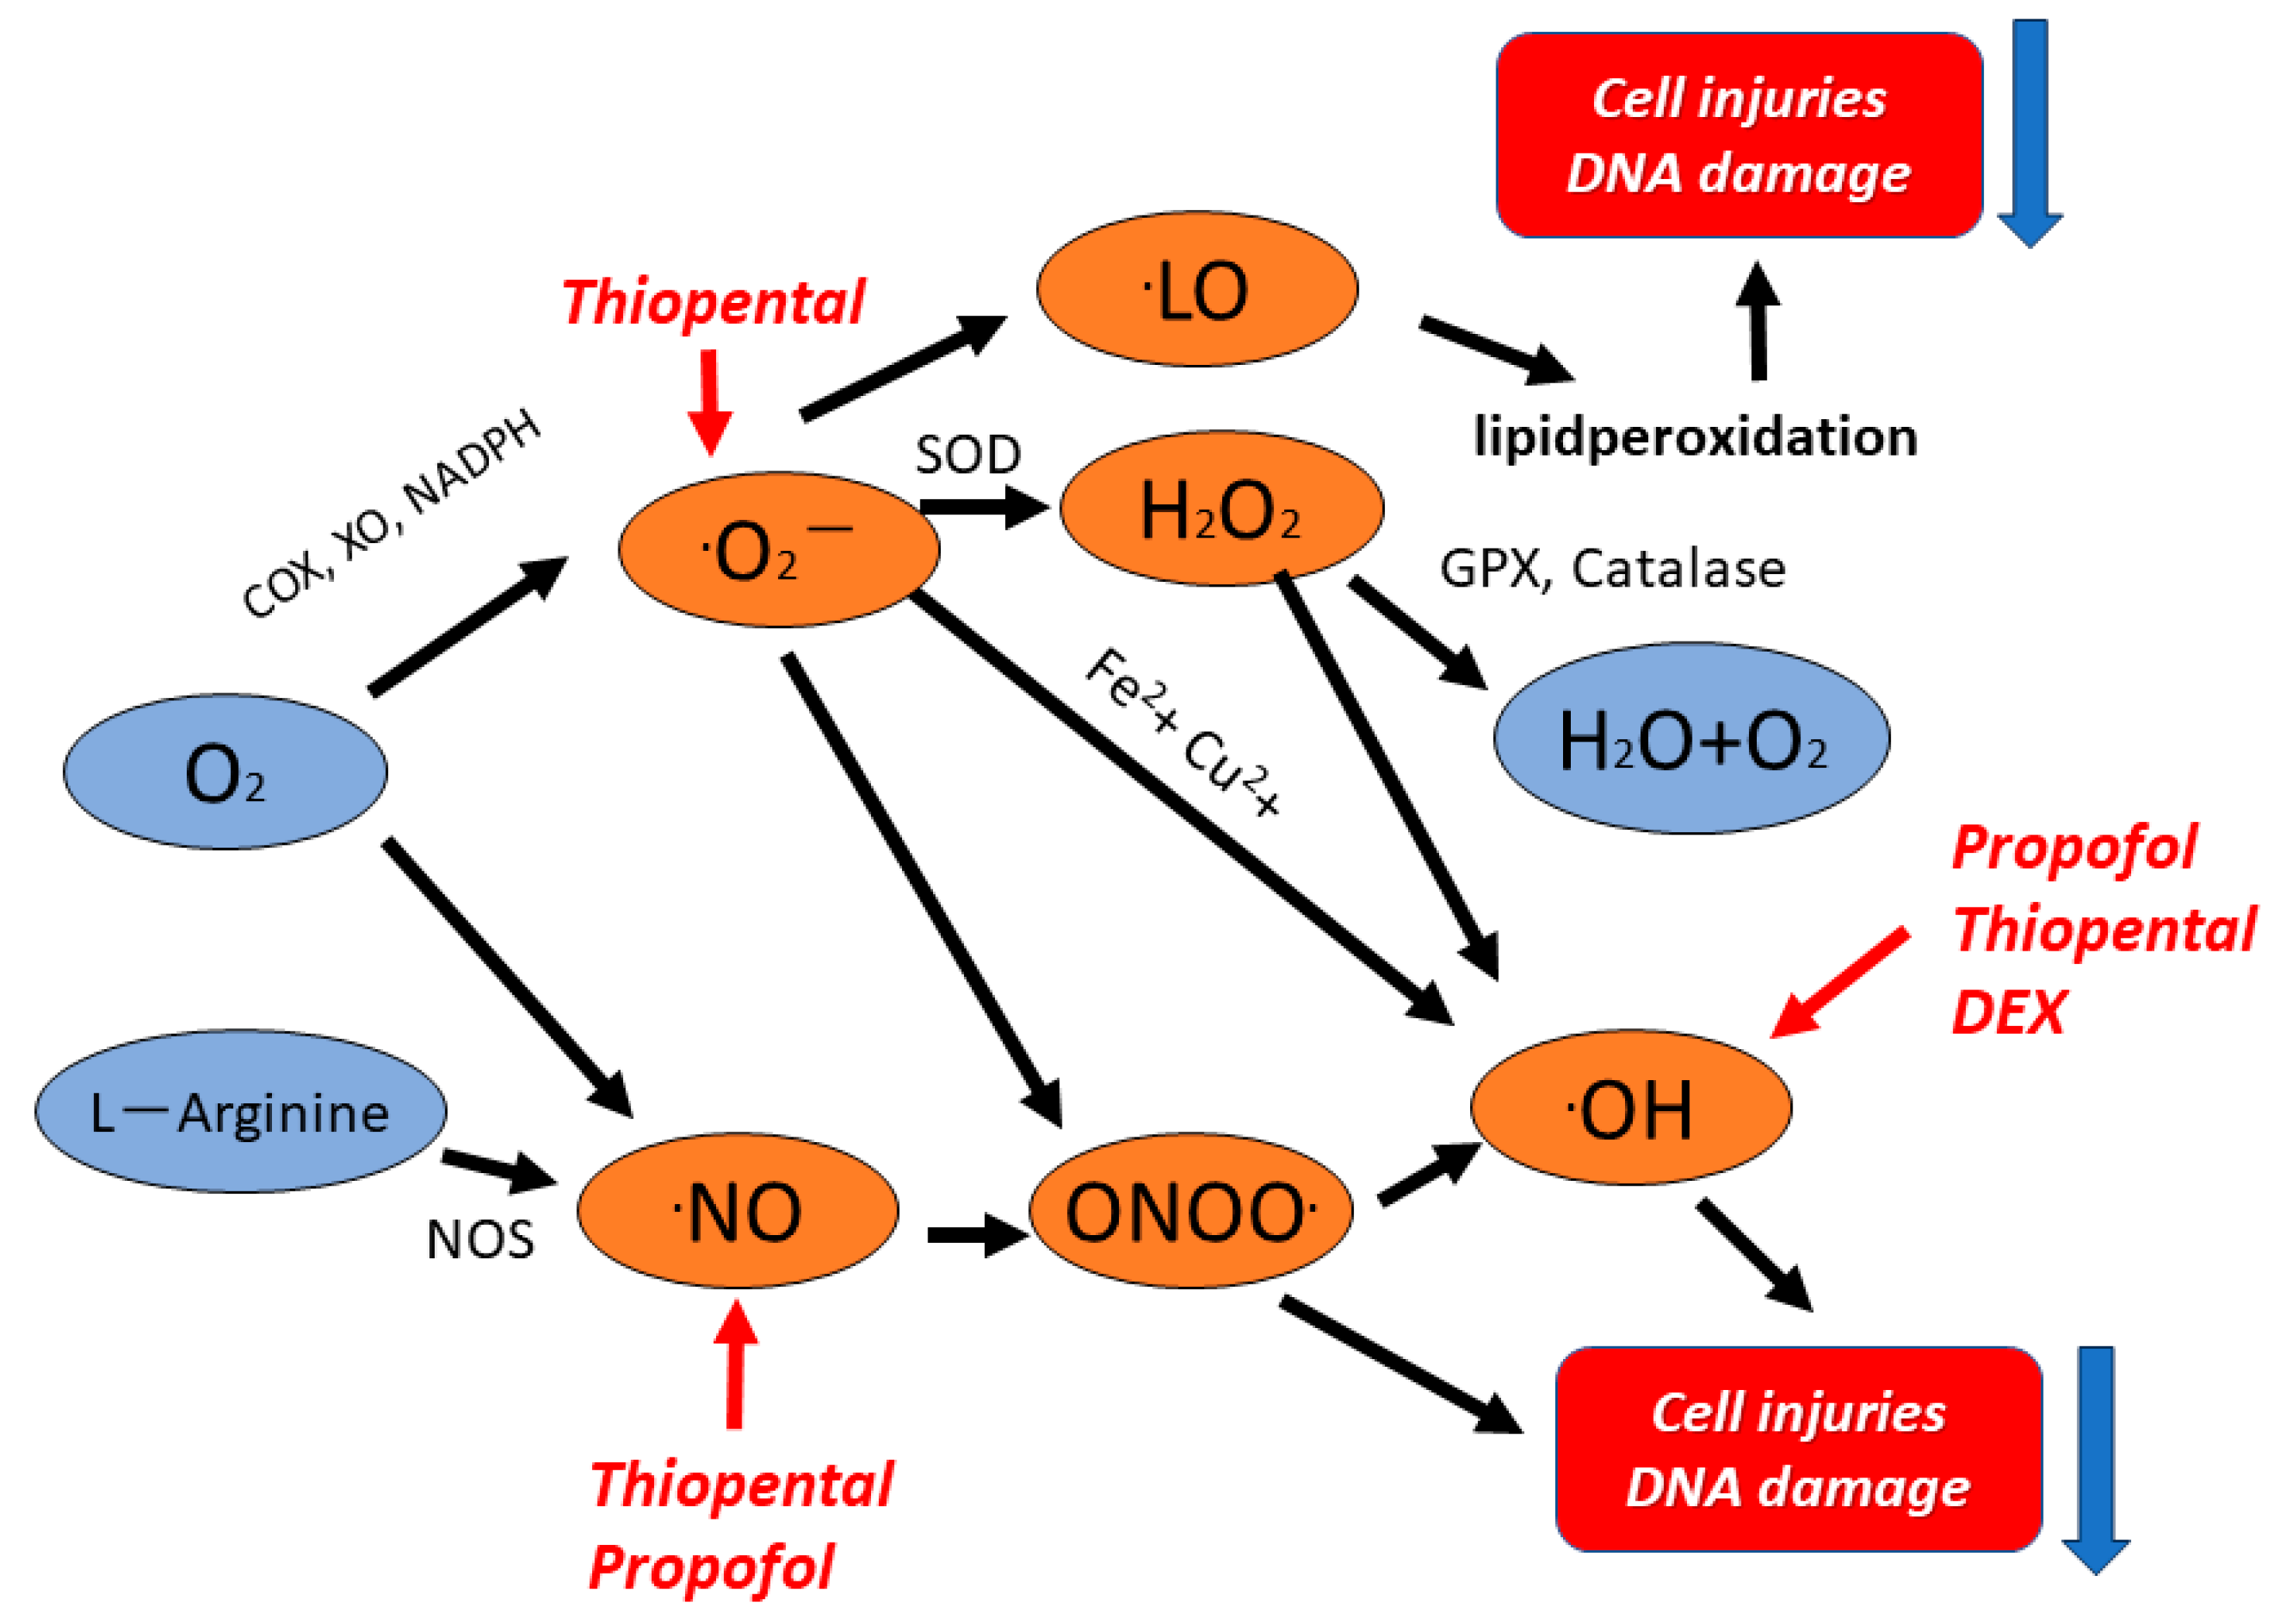

2.2. In Vitro ESR Method

3. Results

5. Discussion